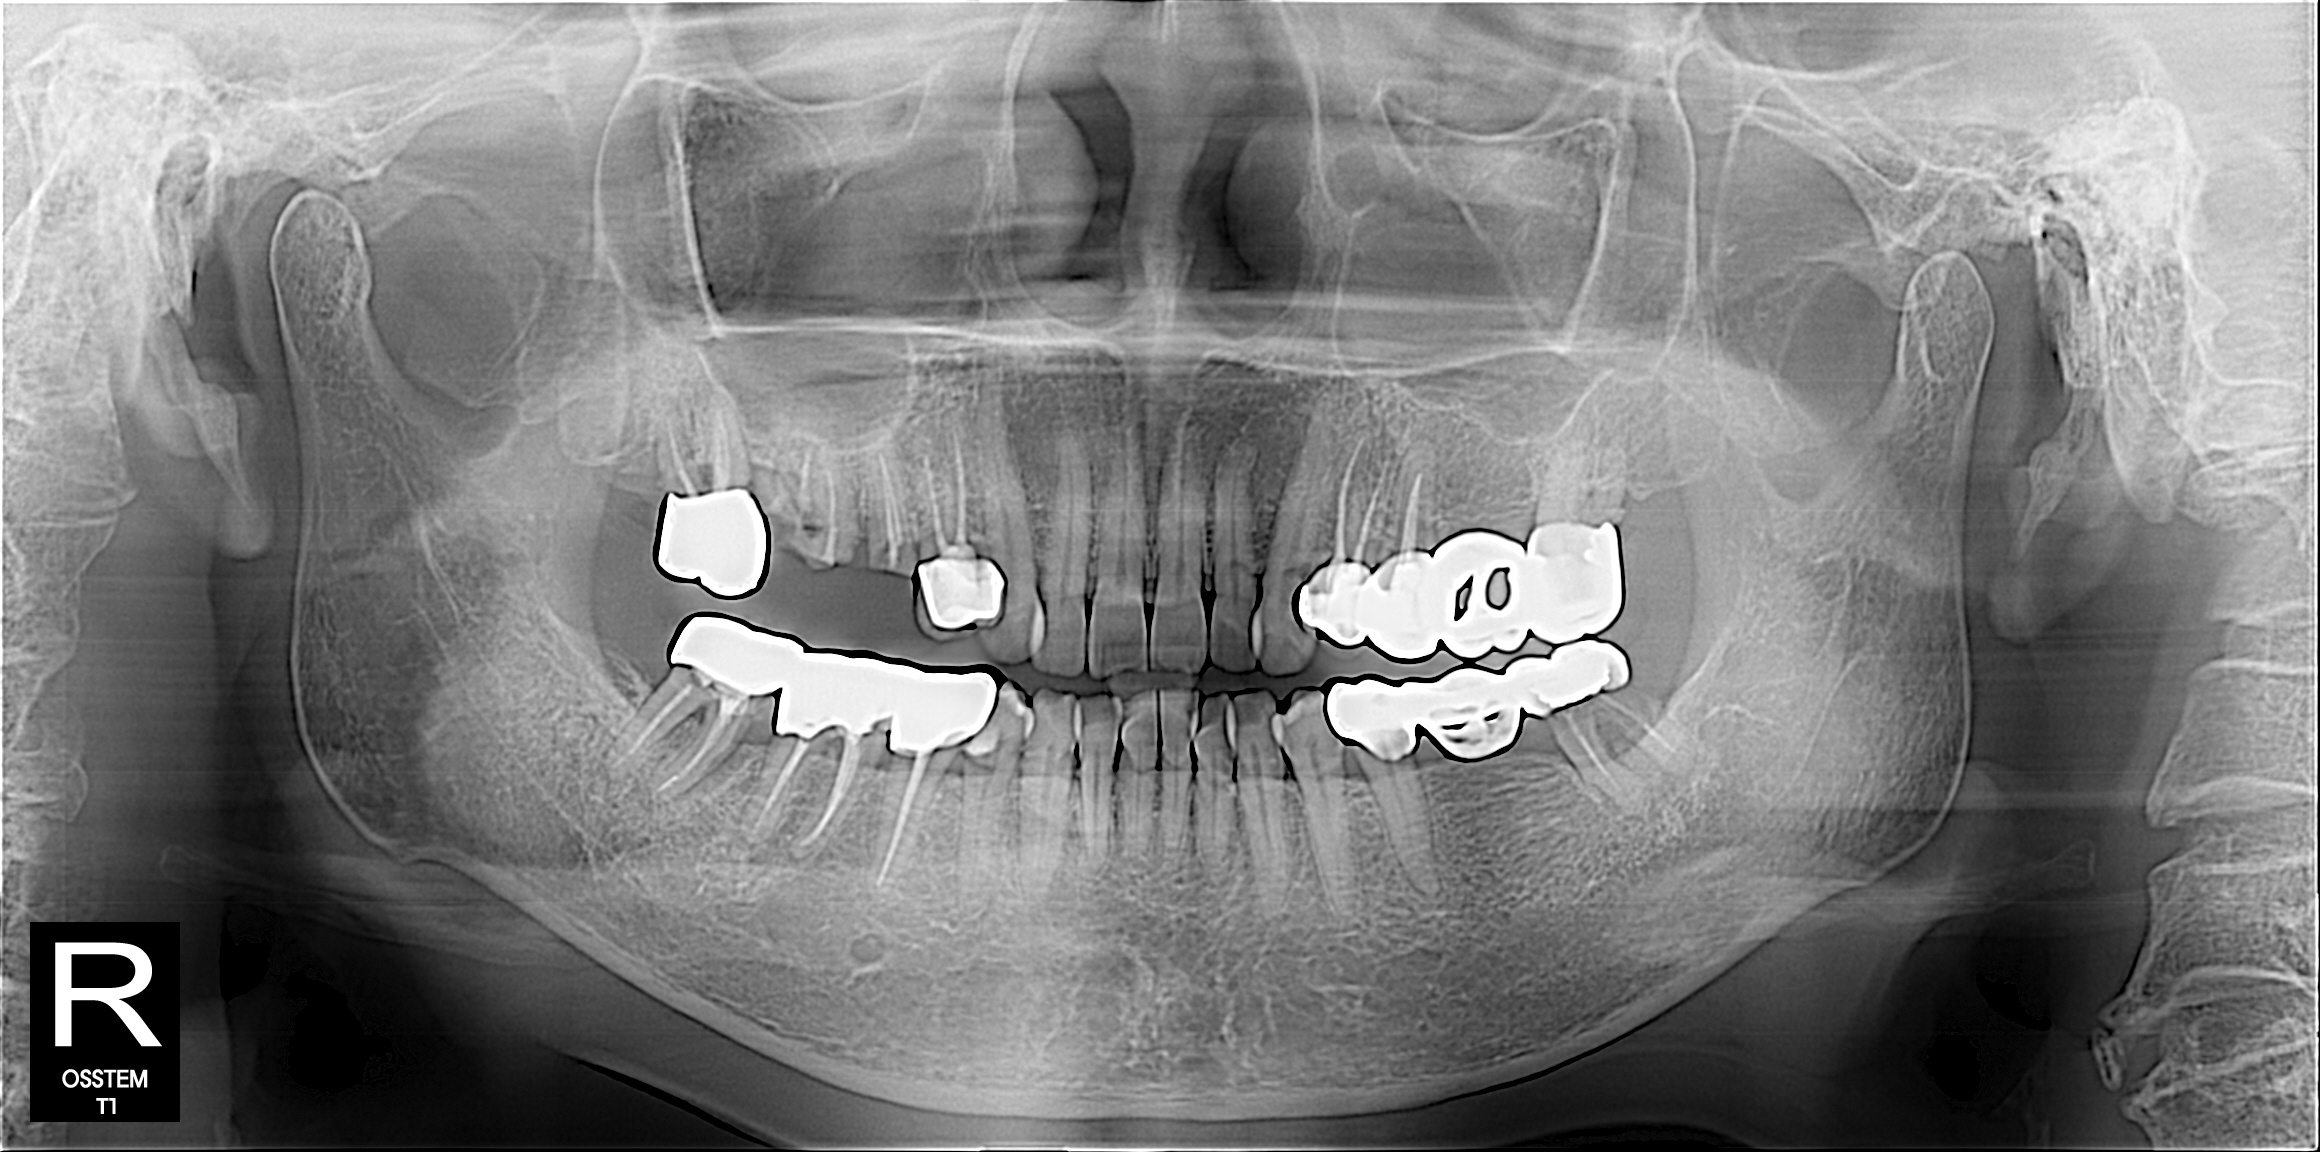

임플란트

BEFORE & AFTER